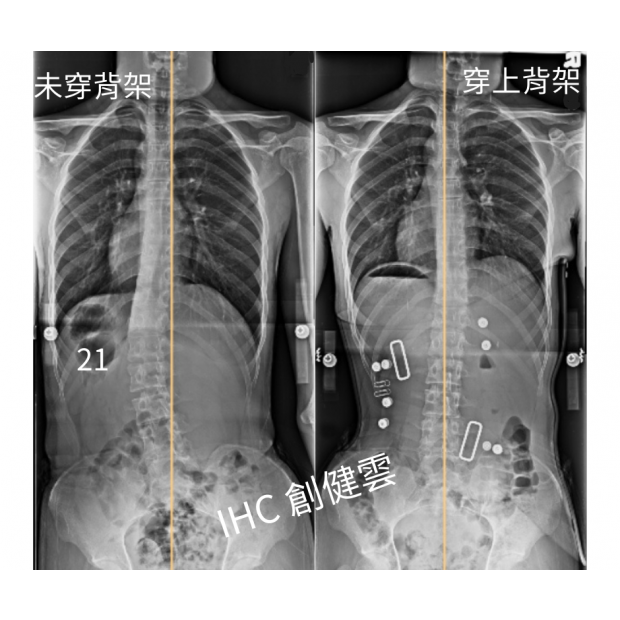

12歲脊椎側彎女孩,腰彎30度

12歲脊椎側彎女孩,腰彎30度 穿上背架後立即矯正效果